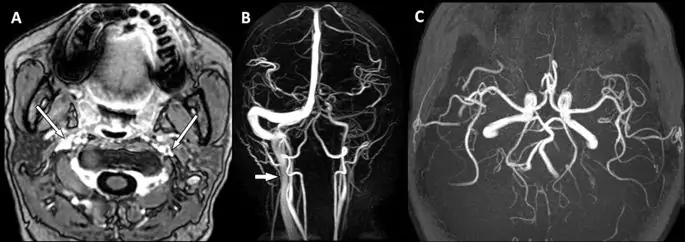

Мы оценили морфологию вен на верхнем IJV (на уровне C1-3) и среднем IJV (на уровне C3-5), используя усиленные по контрасту осевые T1-взвешенные МР-изображения (рис. 2). Мы классифицировали венозную компрессию / стеноз в соответствии с критериями G. Zaharchuk et al. (13) следующим образом: степень 0 = нормальная округлая или яйцевидная форма; степень 1 = мягкое сплющивание; степень 2 = умеренное уплощение; и степень 3 = сильное уплощение или не визуализируется. Показания МРТ всех испытуемых были выполнены одним нейрорадиологом и одним неврологом. Оба были хорошо обучены чтению нейроизображений и были слепы к клиническим характеристикам испытуемых. Консенсусная встреча проводилась для обсуждения любых проблем или разногласий. Коэффициент внутриклассовой корреляции для оценок был использован для оценки межотраслевого согласия с надежностью межотраслевого уровня 0, 76.

фигура 2

Количественная оценка компрессии / стеноза IJV. Усиленные по контрасту аксиальные T1-взвешенные изображения количественной классификации компрессии / стеноза IJV между 0 (нет) и 3 (тяжелые). Примеры на верхнем уровне IJV (C1-C3) демонстрируют отсутствие стеноза (A) или слабого (B), умеренного (C) и тяжелого (D) стеноза (стрелки).

Изображение в полном размере